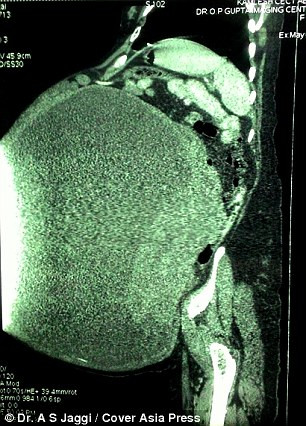

| Phim chụp XQ khối u 97 kg trong cơ thể người phụ nữ đáng thương. |

| Khối u buồng trứng khổng lồ trong cơ thể phụ nữ 45 tuổi. |